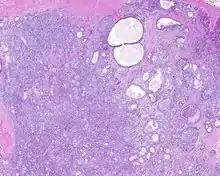

Low power H&E stained image of parotid gland sclerosing polycystic adenoma

When reviewed by a pathologist, the findings are quite similar to fibrocystic changes of the breast, although they are different enough, that it is now recognized to actually represent a true neoplasm (clonal proliferation) through various studies.[5] Specifically, the lesions are usually well-circumscribed, containing lobules of haphazardly arranged ducts, myoepithelial cells, and acini that have abundant sclerosing or hyalinized fibrosis. Apocrine change is quite common in the ductal cells.[6] The ducts range from small ductules to cystically dilated spaces (more than 4 striated duct-widths across), often containing products of secretion or reactive histiocytes. A very curious and characteristic finding in all of the lesions is the presence of bright pink (eosinophilic) acinar granules (which are altered zymogen).